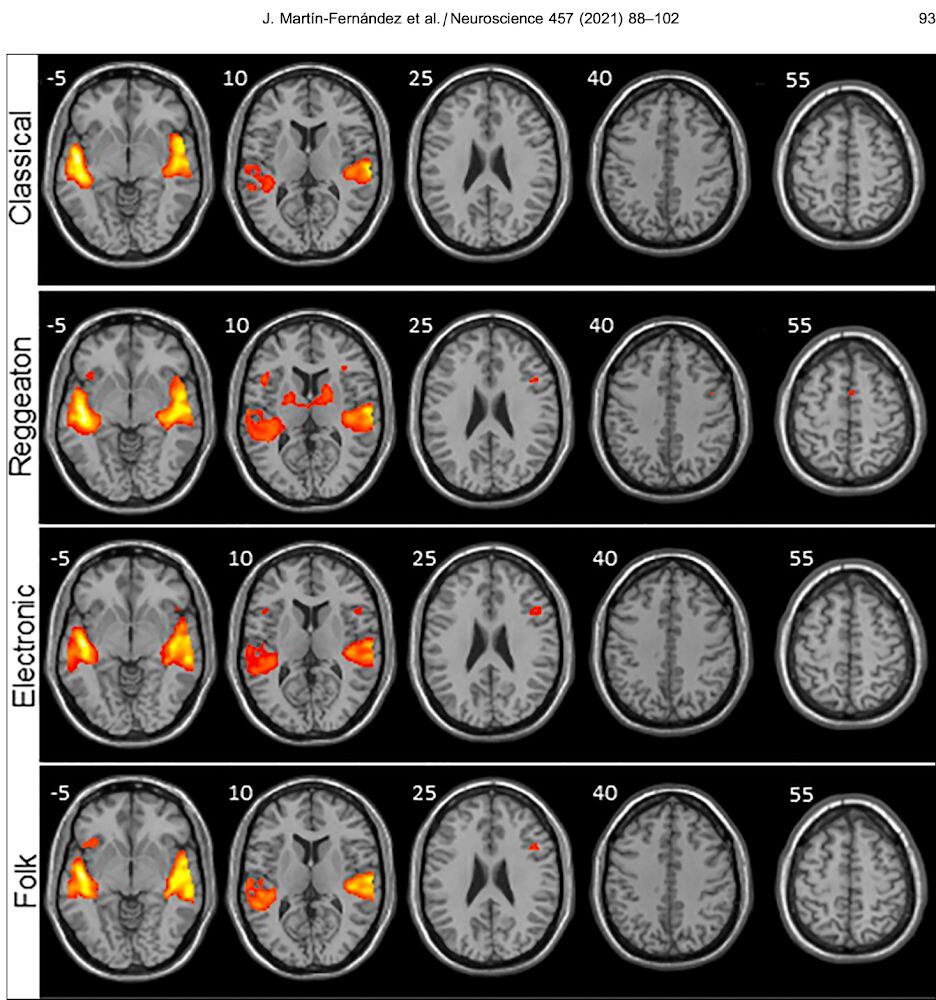

Así, científicos comprobaron que el reguetón fue el género musical que provocó mayor activación cerebral en las regiones encargadas de procesar los sonidos y los movimientos. Para el estudio usaron cuatro géneros musicales: reguetón, música clásica, electrónica y folclore.

Además, el análisis resaltó que la música electrónica también superó a la clásica en términos de activación cerebral de las áreas motoras.

Otro hallazgo importante está relacionado con la activación que se da en la zona de los ganglios basales, estructuras neuronales encargadas de modular la postura y comenzar o finalizar un movimiento, o estar involucrados en el desarrollo del placer. En esta zona también se encuentra el origen de algunas enfermedades degenerativas como el Parkinson.

Cabe señalar que la activación en la zona señala que hay más regiones cerebrales auditivas y motoras que se activan, lo que implica que existe una mayor maquinaria trabajando en procesar la música. Según reseñan los expertos, la activación de las zonas encargadas del movimiento se puede relacionar a que se genera un pulso interno dentro de cada persona que buscar adivinar el siguiente ritmo de la canción.